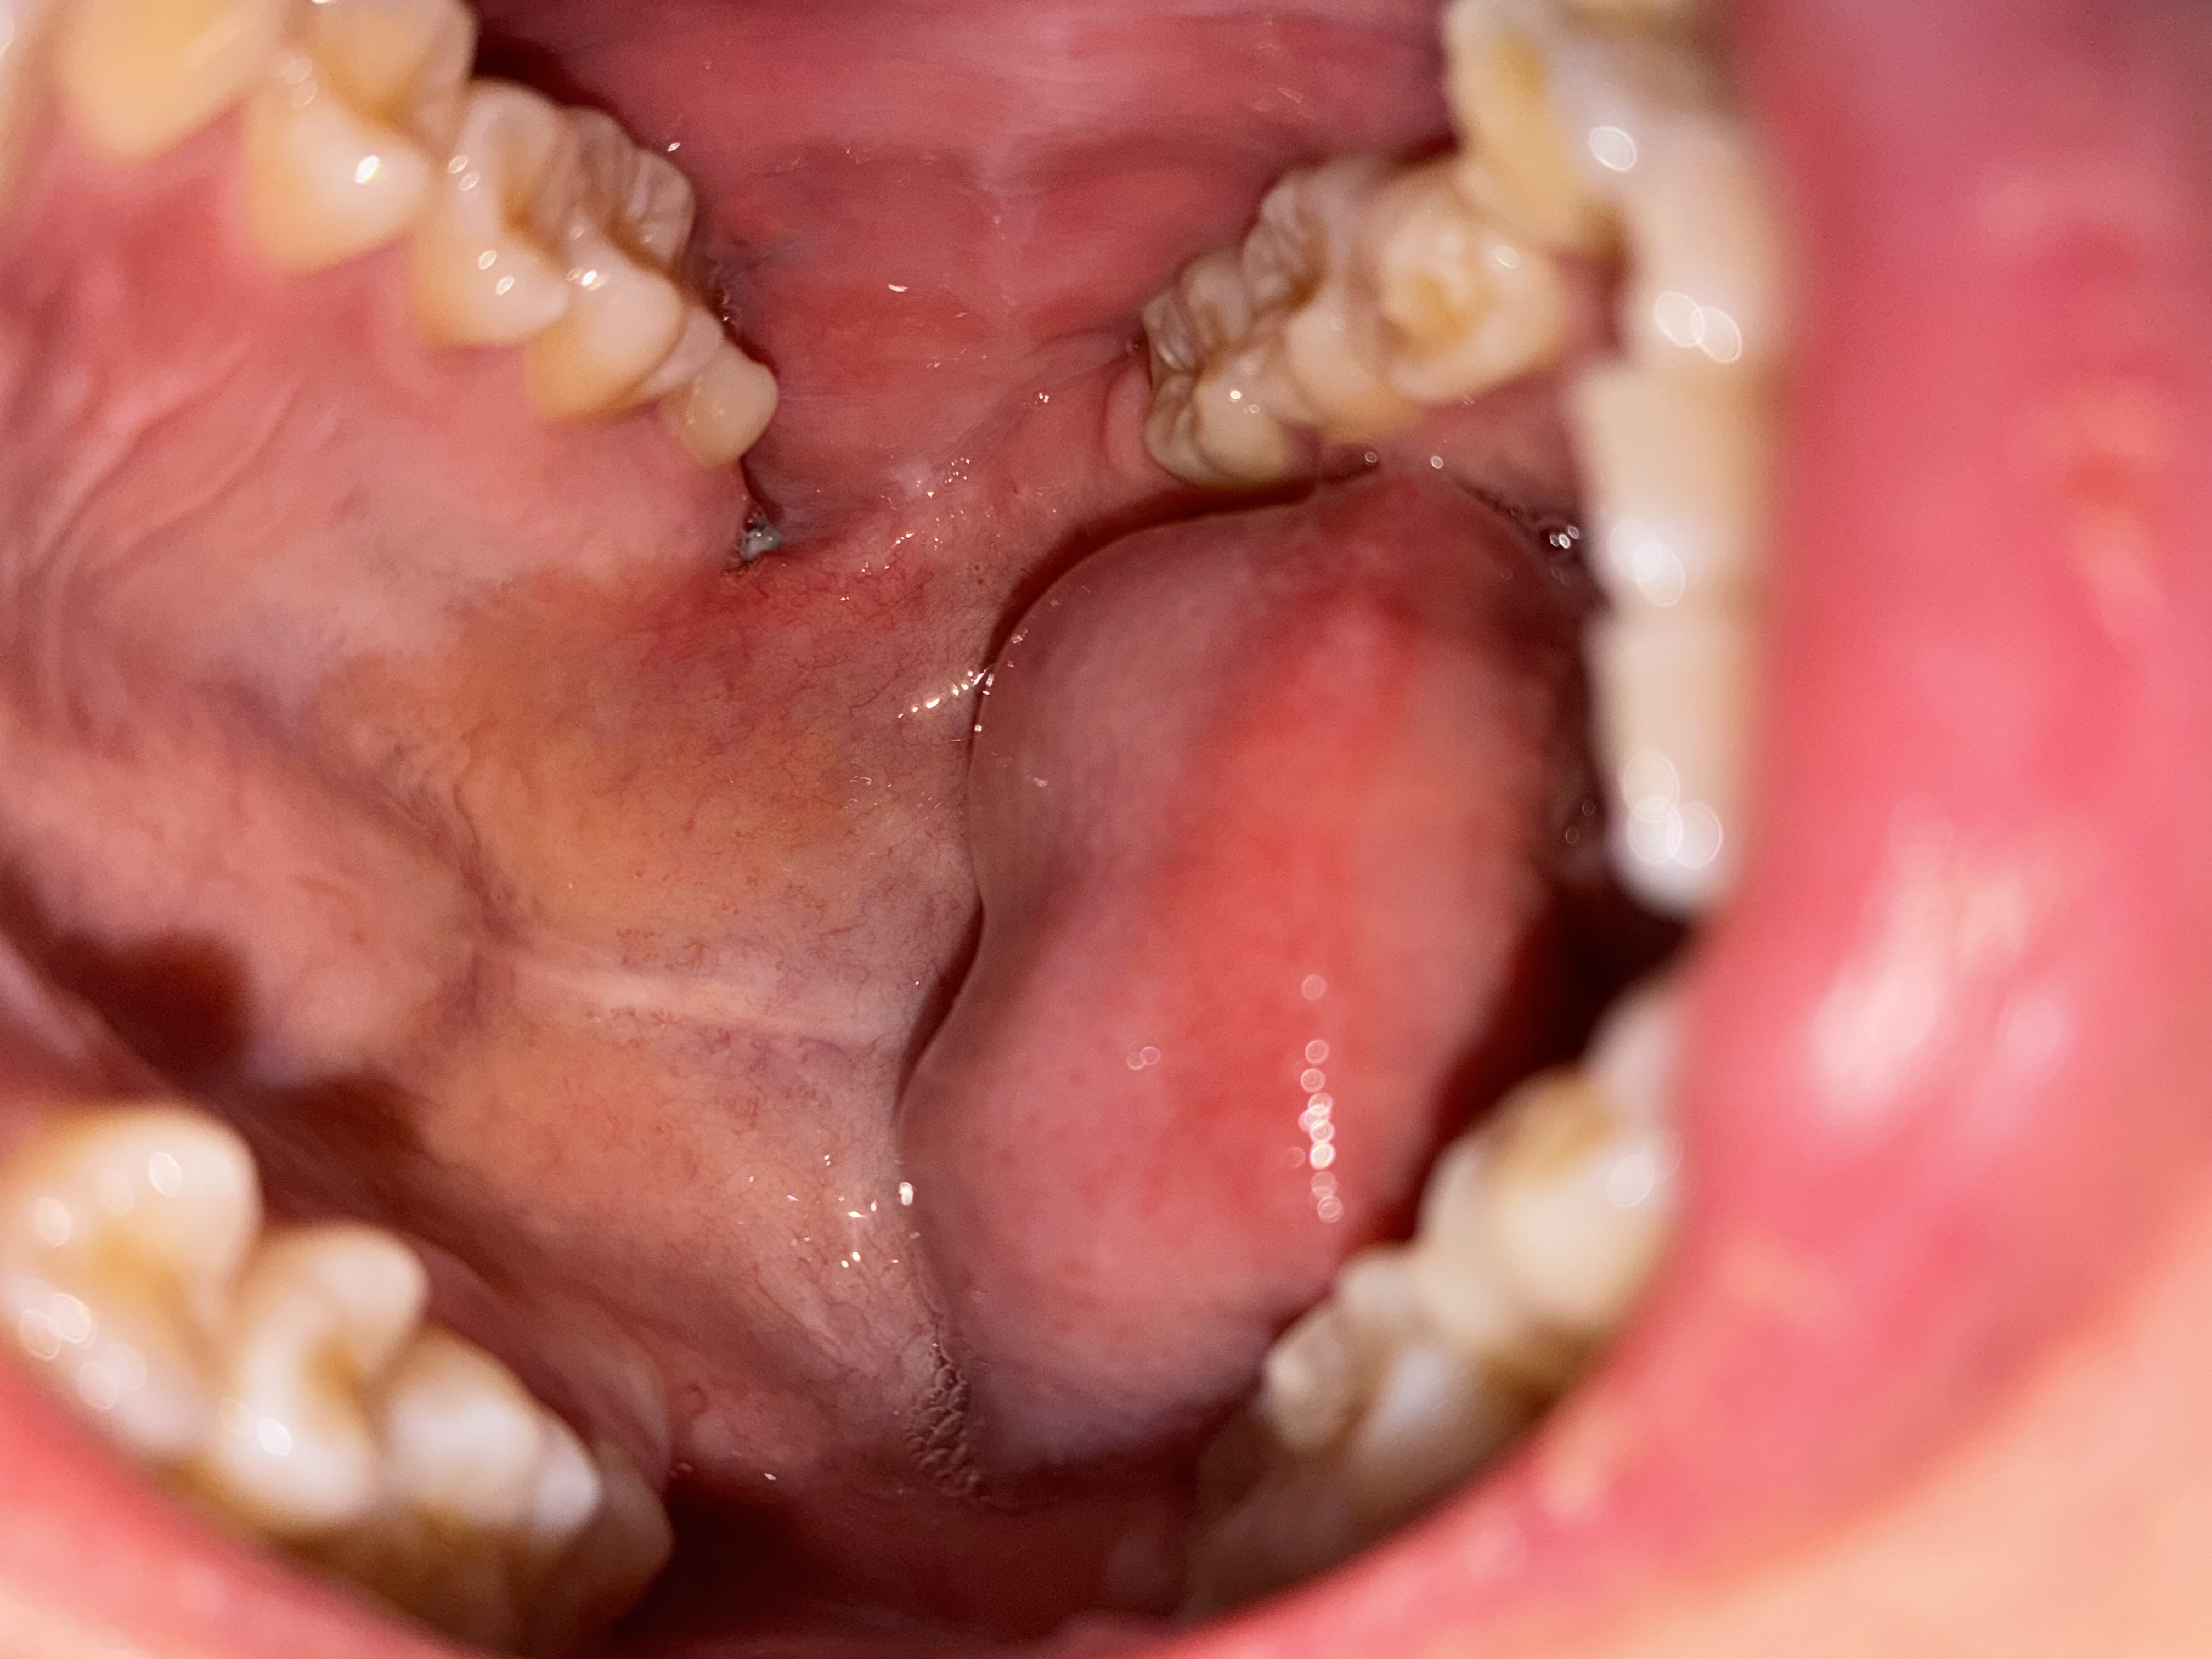

抜歯後に縫合した内頬に痣のようなものが出来て突っ張る感じと痛みがあります。